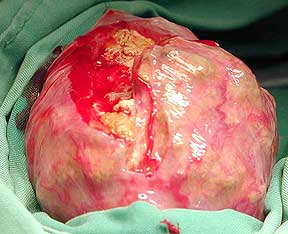

The bladder is gently exteriorized through

the hole in the shell. Dr. Ridgeway has made an incision into

the bladder and the stone is starting to bulge out.

- 小心的把膀胱由腹甲切口中提出來,Ridgeway醫師

- 已經在膀胱上做了一個切口,露出了結石

Here is the culprit as it is being removed from

the bladder.

這就是整個挖出來的結石